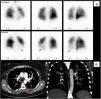

In 2013 (aged 40), at a routine follow-up appointment, she complained of severe exertional dyspnea and palpitations. Physical examination revealed central cyanosis and tachycardia, and peripheral capillary oxygen saturation (SpO2) was under 90%. Blood tests showed polycythemia and elevated N-terminal pro-B-type natriuretic peptide (NT-proBNP). Doppler TTE showed an estimated PASP of 100 mmHg (normal <35 mmHg7) and she was promptly referred to a specialist pulmonary hypertension center. Further investigations were as follows: pulmonary function tests were normal; the six-minute walk test (Table 1) revealed normal chronotropic and inotropic competence on exertion but reduced functional performance (75% of normal)8; the pulmonary ventilation/perfusion scan (Figure 1A) indicated subsegmental perfusion defects with preserved ventilation of all the left lobe segments and of the superior and posterior basal segments of the right lobe; CT angiography (Figure 1B) showed a subocclusive stenotic lesion at the origin of the left inferior lobar artery and bilateral involvement of lobar and peripheral branches; right heart catheterization (Table 1) disclosed low cardiac output and index, elevated mean pulmonary artery pressure, pulmonary vascular resistance three times the upper limit of normal, and pulmonary artery wedge pressure below the threshold, overall indicative of moderate precapillary PH; and pulmonary angiography (Video 1) showed multiple filling defects with total occlusion of the left inferior lobar artery in addition to several segments of the right superior and inferior lobes.

Initial diagnostic procedures. (A) Pulmonary ventilation/perfusion scan with subsegmental perfusion defects (blue arrows) and preserved ventilation in the left lower lobe; (B) computed tomography angiography with a subocclusive stenotic lesion at the origin of the left inferior lobar artery (red arrows). Ant_P: anterior-posterior; L: left; Post-P: postero-posterior; R: right; RPO_P: right posterior oblique-posterior.